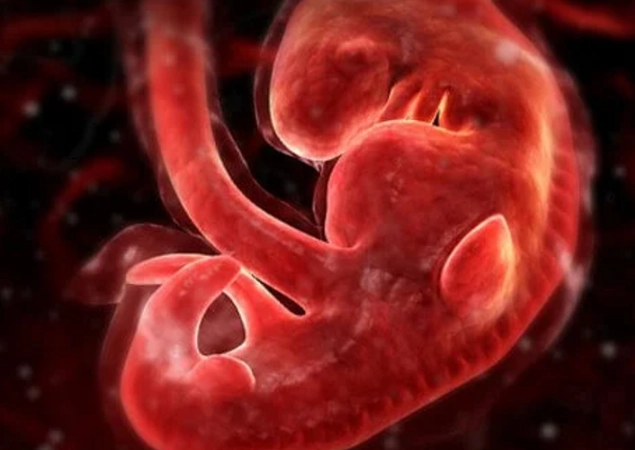

The Basics: What's Actually Happening at 4 Weeks?

First, a tiny bit of science to ground us. At four weeks pregnant, you're technically in the second half of your first month. Conception happened about two weeks ago. Right now, the fertilized egg has travelled and implanted itself in your uterine lining. It's now called a blastocyst, and it's busy dividing like crazy. The part that will become the placenta is starting to form and produce the pregnancy hormone hCG (human chorionic gonadotropin).

This hCG is the star of the show. It's the hormone that turns a pregnancy test positive, and it's largely responsible for many of the early symptoms you might start to notice. Your body is just beginning to ramp up production, so levels are still relatively low but rising fast.

Fun (and slightly weird) fact: Even though you're called "4 weeks pregnant," you've only actually been pregnant for about 2 weeks. Pregnancy dating starts from the first day of your last menstrual period (LMP), not from conception. It's confusing, I know. The medical world works in mysterious ways.